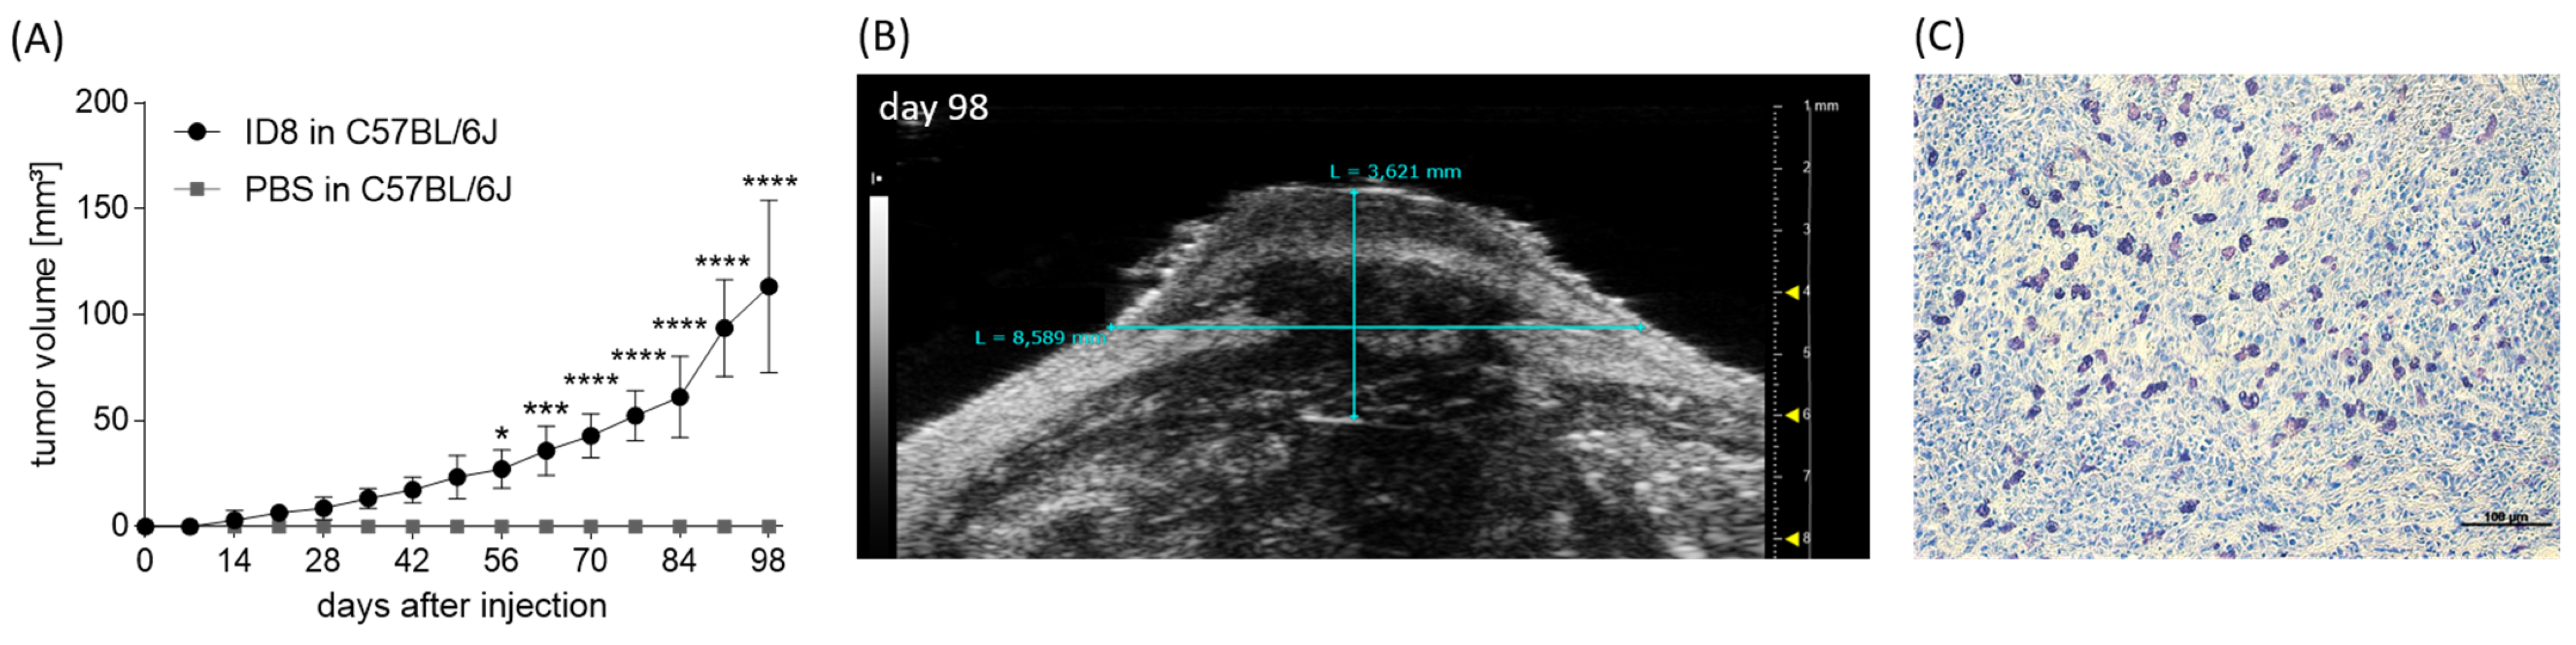

3.1. MCs Are Present in Human Ovarian Cancer Samples

3.3. Optimization of an In Vivo Model to Study the Participation of MCs in Ovarian Cancer Growth